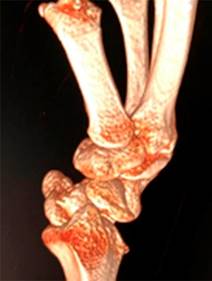

Masculino de 23 años de edad, sano, quien sufre caída del propio plano de sustentación contundiendo mano derecha con mecanismo de hiperflexión. Inicia con dolor, limitación funcional y edema importante en muñeca, motivo por el cual acude al servicio de urgencias. A la exploración física, llama la atención edema y deformidad en dorso de muñeca derecha con limitación funcional a expensas del dolor, sin alteraciones neurovasculares distales. Se realizan radiografías en proyecciones anteroposterior y oblicua de mano (Figura 1); se observa incongruencia entre líneas carpales con sospecha de fractura de escafoides. Se realiza tomografía computarizada (Figura 2), con la cual se completa diagnóstico de fractura luxación transescafo-perilunar.

Figura 2: Reconstrucción 3D de tomografía axial computarizada. Se observa fractura-luxación transescafo-perilunar.